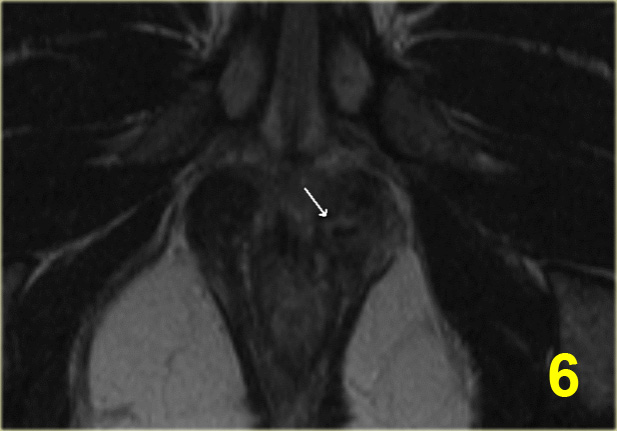

Bên trái là một ví dụ về rò trên cơ thắt.

Có hai đường rò trong vùng hố ngồi-hậu môn.

Đường rò bên phải chạy qua cơ mu-trực tràng (dấu hoa thị) và lỗ mở niêm mạc nằm ở

mức đường lược (mũi tên đen).